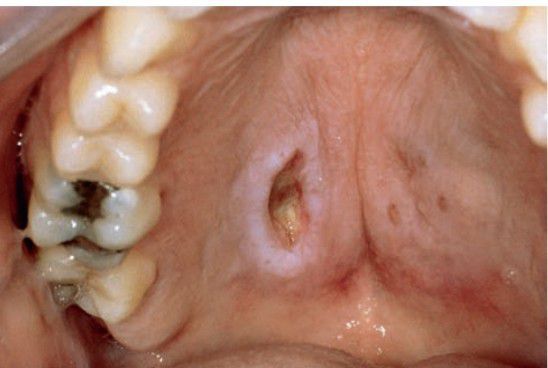

Neutrotizing sialometaplasia

Intraorally, necrotizing sialometaplasia is most common at the junction of the hard and soft palates . Early in its evolution, the lesion may be noted as a tender swelling, often with a dusky erythema of the overlying mucosa.